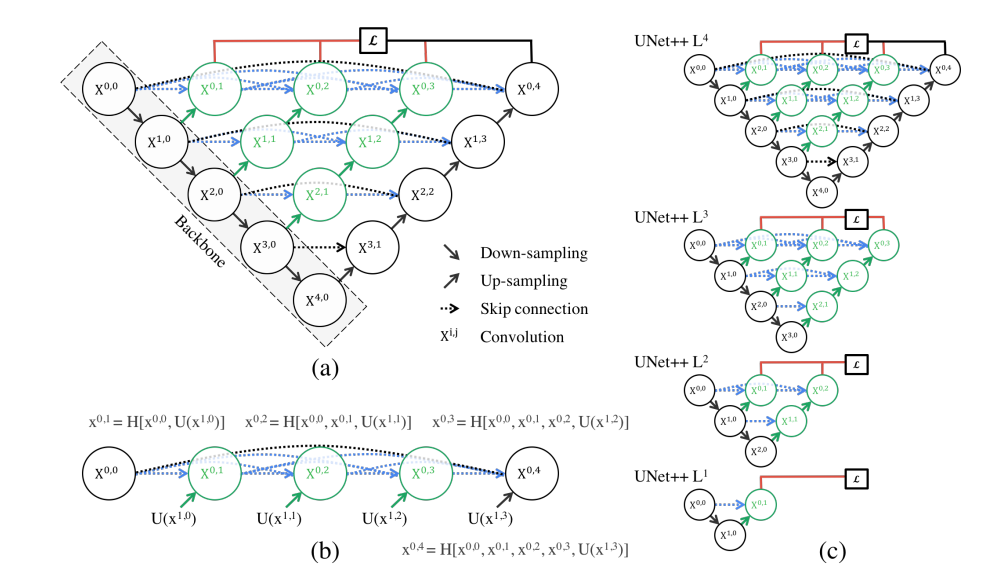

U-Net++ 是一种改进的 U-Net 分割网络,其主要目标是通过更加细粒度的特征融合与密集的跳跃连接(Dense Skip Connection)机制,进一步提高分割性能。U-Net++ 的设计在 U-Net 的对称编码器-解码器架构基础上进行了增强,使得不同分辨率的特征能够在网络中得到更细致的交互和融合。

U-Net++ 的核心特点在于使用了嵌套和密集的解码路径(Nested and Dense Decoders),同时改进了跳跃连接机制。在传统 U-Net 中,跳跃连接直接将编码器和解码器中相同分辨率的特征进行拼接。而在 U-Net++ 中,跳跃连接由密集卷积模块(Dense Convolution Blocks)代替,使得不同分辨率的特征可以通过逐层细化路径进行多次融合和传递。

U-Net++ 的编码器部分通过一系列卷积、激活(如 ReLU)、批归一化(Batch Normalization)以及最大池化操作提取多尺度特征,与传统 U-Net 相似。但在编码器和解码器之间的跳跃连接上,每一对相邻分辨率的特征图通过一系列密集卷积块逐步传递,而不是简单的直接传递。这些密集卷积块形成了一个嵌套结构,其中高层次特征可以被逐步细化和补充,最终在解码器部分实现更加精准的分割。

解码器部分逐步恢复特征图的空间分辨率,并结合从编码器传递来的多层特征。与传统 U-Net 不同的是,U-Net++ 的解码路径由多个级联的解码子路径组成,这些子路径通过共享特征融合的信息层层优化特征表示。这样,网络能够有效地综合浅层特征的细节信息和深层特征的语义信息。

输出层采用 1x1 卷积,将解码器最终的特征映射到与分割类别数相同的通道数。结合 Sigmoid 或 Softmax 激活函数,生成每个像素的分割概率图。

U-Net++ 的主要优点是通过密集跳跃连接和嵌套解码路径增强了特征的重用性与细粒度融合,使网络对边界复杂的目标区域具有更强的分割能力。此外,这种设计还提升了模型的鲁棒性和泛化能力,特别适合应用于医学图像分割任务中的复杂形态学特征提取。